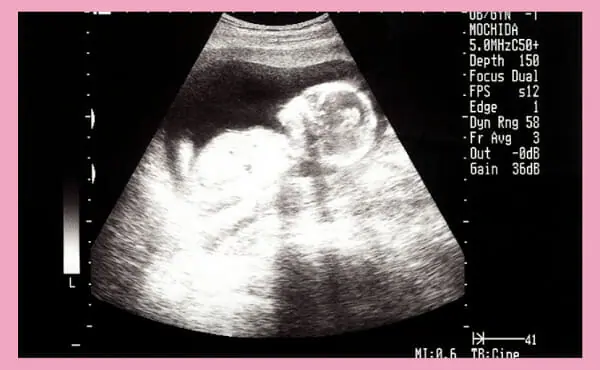

妊娠第15周的超声照片。

妊娠15周通过超声检查可以看到什么

孕期的超声检查在妊娠4〜11周时经阴道进行,从妊娠12周开始,超声检查在腹部进行。

妊娠15周时,胎儿的外生殖器已经形成,在超声检查时通常可以通过胎儿的身体方向,来确定胎儿的性别。有些医疗机构可能无法提供超声波的性别鉴定结果,所以最好提前确认。